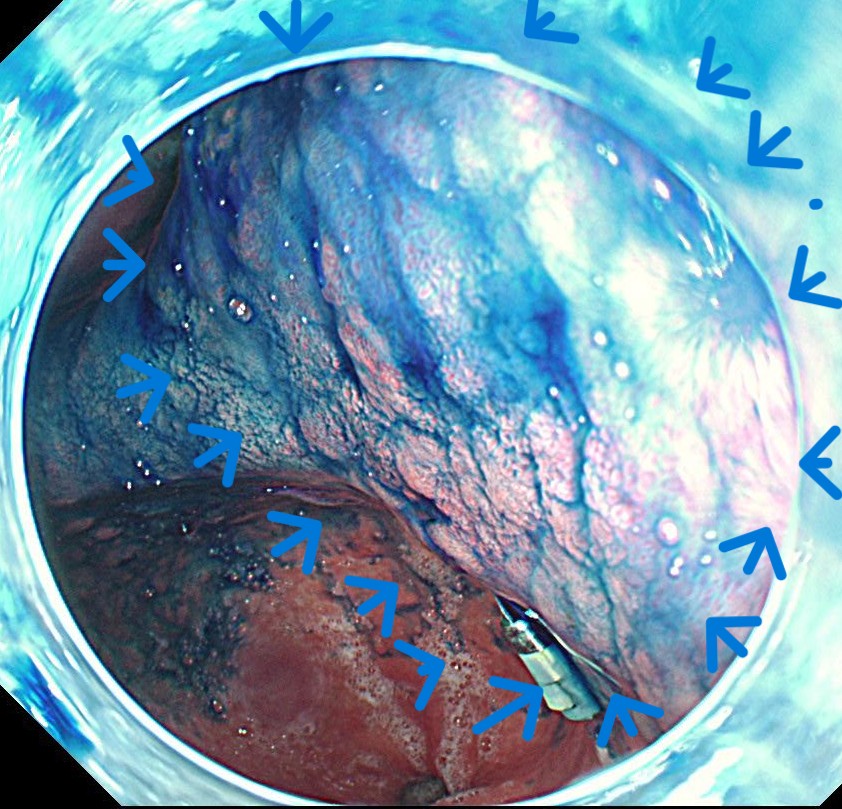

インジゴ散布で腫瘍の凹凸ははっきりします。

まずは腫瘍を取り囲むようにマーキングします。バイオ300のソフト凝固でマーキングしています。